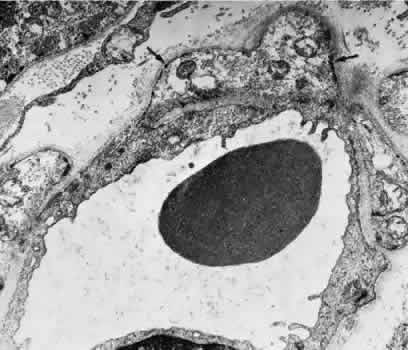

The vessel walls themselves consist of fenestrated endothelium surrounded by a basement membrane and a sparsely arranged layer of pericytes. The portion of the endothelial cell containing the nucleus also contains most of the cell's cytoplasm and organelles. The remainder of the cytoplasm is extremely attenuated, and these regions contain the fenestrae. These fenestrae are approximately 700 to 800 nm in diameter and are covered by a diaphragm. The attenuated areas are most typically found facing the RPE and contain very few pinocytotic vesicles. The region of the cell facing the suprachoroidal space usually contains more cytoplasm, fewer fenestrae, and the nucleus (Fig. 14). Few pericytic processes are seen in cross sections of these vessels on the side of the vessel facing the pigmented epithelium (Fig. 15). However, these processes are more numerous on the surface of the vessel facing the sclera. Because of the fenestrae, the choriocapillaris actively leaks fluorescein molecules.

Fig. 14. Electron micrograph. A. A portion of the capillary wall facing the suprachoroidea. The endothelial layer is relatively thick, and few fenestrae are present. Several pericytic processes (arrows) may be seen. B. A portion of the capillary wall facing the pigmented epithelium. Numerous fenestrae may be seen in the attenuated endothelium. The elastica of Bruch's membrane is well developed (EI).